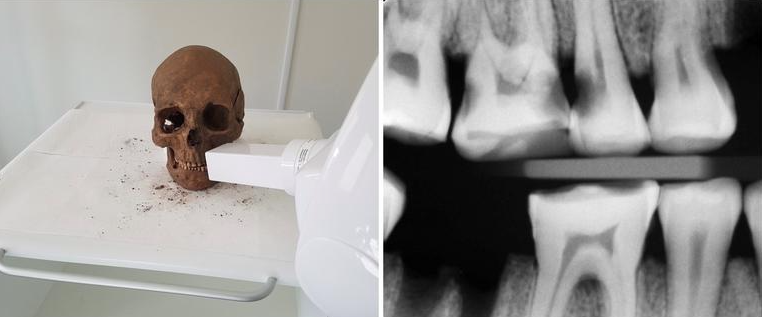

Para este trabajo, se examinaron casi 3.300 dientes de 171 individuos de entre los siglos IX y XI aproximadamente, provenientes de un yacimiento donde las condiciones del suelo han permitido que los cuerpos se conservaran en buen estado. Las piezas fueron estudiadas usando técnicas y herramientas modernas de odontología, y las conclusiones han sorprendido los investigadores.

Los resultados de las pruebas, pues, muestran que las caries, las infecciones y otros problemas que causan dolor en la boca eran bastante habituales entre los vikingos. Sin embargo, el mismo estudio también muestra que miraban de tratar estos males de varias maneras. Así, los análisis han mostrado indicios del uso de palillo, de haber limado algunas piezas e incluso de tratamientos para infecciones.

Uno de los procedimientos más sofisticados de que se han encontrado pruebas es, sorprendentemente, limar agujeros de las muelas, desde la corona y hasta bajo de todo, una técnica que probablemente se usaba para reducir la presión y el dolor en casos de infección. Un tratamiento que, al fin y al cabo, no es muy diferente del que se lleva a cabo cuando se barrena un diente infectado, cosa que hace pensar que tenían algunos conocimientos rudimentarios de salud bucodental. Un hecho sorprendente no solo porque los individuos analizados hace más de 1.000 años que murieron sino, también, porque rompe la imagen de los vikingos como un pueblo de guerreros bárbaros.